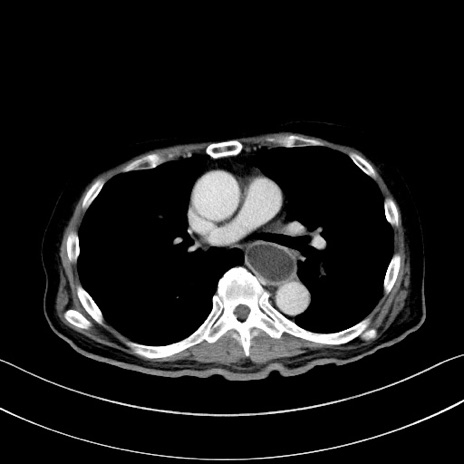

症例28(横断像)

【症例】60歳代男性

【主訴】嘔吐

【現病歴】胃癌にて胃全摘後。食思不振が悪化し、夜中に嘔吐することがある。

【既往歴】胃癌、胃全摘、脾摘、胆摘後

【データ】WBC 5900、CRP 10.56